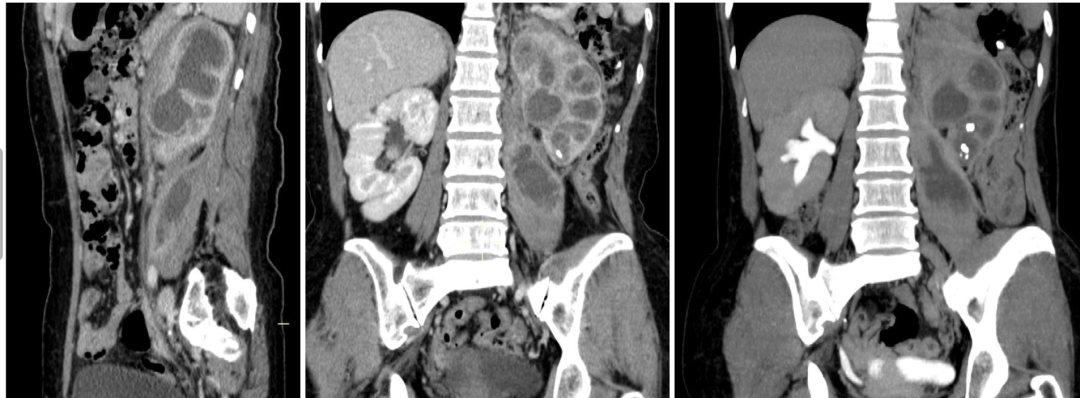

"熊掌征"(bear paw sign)是指在断面影像上肾盂粘连收缩,而肾盏扩张,肾皮质变薄,扩张的肾盏形似熊脚掌的征象,它是黄色肉芽肿性肾盂肾炎的一个重要特征性征象。

黄色肉芽肿性肾盂肾炎是一种慢性肉芽肿过程,被认为是亚急性/慢性感染导致慢性但不完全免疫反应的结果。最常见的是大肠埃希菌和奇异变形杆菌感染。其特征是肾实质损害、肉芽肿性脓肿及肾间质大量含脂肪的巨噬细胞聚积。含脂肪的巨噬细胞堆积。肾脏最终被大量反应性组织取代,伴有不同程度的肾积水,其环绕鹿角形

"熊掌征"表现为以肾盂肾盏为中心肾实质内多发囊性占位,其中部分囊为结石梗阻所致的肾积水,部分为黄色肉芽肿的脓腔;通常肾盏扩张为主,肾盂扩张常常不显,增强后,病变实性部分均匀强化,坏死区无强化,低密度区边缘环形强化。患肾体积增大或局限性隆起。常常伴有集合系统结石;肾皮质变薄;肾窦脂肪组织减少,多为慢性炎性反应性纤维组织增生所替代;肾周筋膜增厚、肾周间隙渗出积液,严重时可形成脓肿累及腰大肌。腹部X线平片典型的表现是受累的肾脏增大并有鹿角状结石,同侧腰大肌边缘模糊。超声显示肾脏轮廓变形,正常结构消失,中央可探及结石声影。